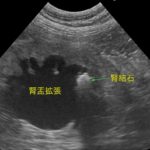

超音波検査で左右の腎盂が著しく拡張していたので、そのまま、無麻酔CT検査を行い左右の尿管結石による左右の腎盂拡張が確定されました。直ちに経皮的腎盂穿刺により、腎後性高窒素症、代謝性アシドーシス、高カリウムの補正を行いました。来院から約36時間で高カリウムが消失し、血液データが改善してきたことから、両側同時にマイクロサージェリーで尿管切開により結石摘除を行いました。術後は結石が閉塞していた影響で尿管炎が顕著になるため、尿管狭窄を予防するために、尿管内に一時的ステント留置を行いました。数週間後に再び麻酔下でステント抜去を行います。また、症例によって腎下方移動尿管膀胱吻合術に移行する場合もあります。徐々に腎数値も良化し、尿も沢山排泄されているようで一安心です。